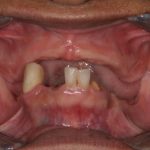

The clinical changes observed when an edentulous maxillary arch is opposed by a mandible with retained anterior teeth that may or may not be extruded and missing posterior teeth. Over time, there is a loss of bone in the premaxilla and in the edentulous posterior mandible, overgrowth of the maxillary tuberosities, and hyperplasia of the hard palate mucosa. Also referred to as anterior hyperfunction syndrome, or Kelly syndrome.